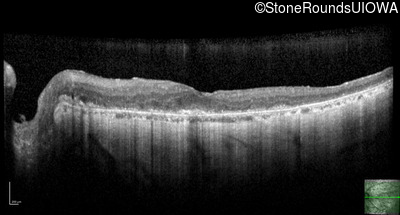

Optical Coherence Tomography - Left - 20/80 -1

Exemplar / OCT Stack